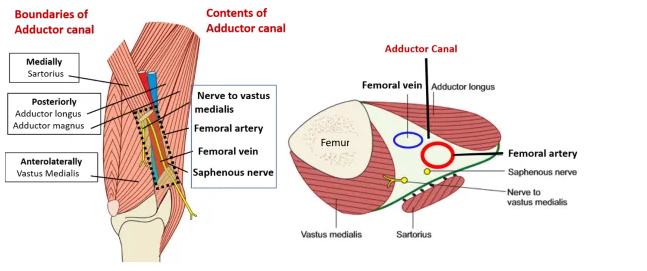

Canal de Hunter Contient:

- Artères fémorale superficielle (devient poplitée à sa sortie)

- Veine fémorale superficielle

- Nerf saphène